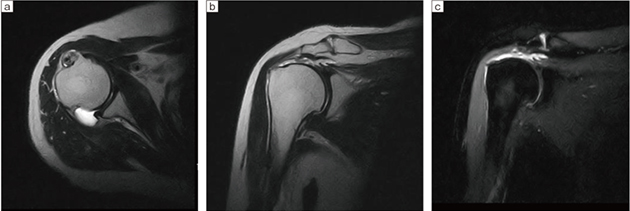

■症例1:右肩腱板損傷

a:T2WI アキシャル,2D DE FSE,TR/TE=3805/100,スライス厚:4.5mm,FOV:180,

マトリックス:256×192,撮像時間:4:08

b:T2WI コロナル,2D DE FSE,TR/TE=3805/100,スライス厚:4.5mm,FOV:180,

c:STIR コロナル,2D DE FSE,TR/TE=3500/25,スライス厚:4.5mm,FOV:180,

マトリックス:192×160,撮像時間:4:58